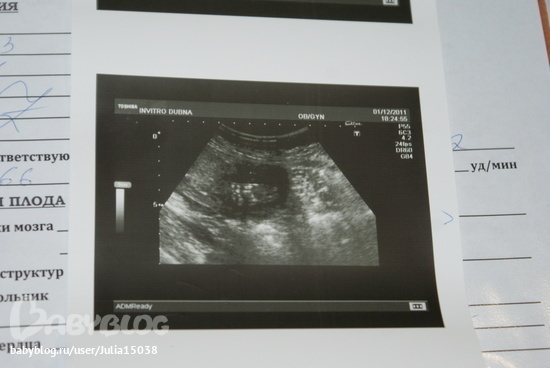

Узи в 20-21 недели

Результаты: УЗИ, КТГ, доплера, скринингаУстала ждать нашего узи,которое должно было быть только 22 декабря, не удержались и пошли мы всей семьей. Очень меня обрадовало,то что малыш здоров, все хорошо(я переживала что часто болею простудными заболеваниями). Сказали МАЛЬЧИК, я была в таком шоке,так как всю жизнь мечтаю что будет дочка у меня, но не в этот раз(((. А ведь все календари по определению пола,говорят что будет девочка,тьфу на эти календари,врут они все.Вес малыша 366гр, роды на 17 апреля.Когда делали узи,малышу это явно не понравилось, он активно отпинывал этот датчик ))).А вот и фото,на одном фото он лежит и смотрит на нас,а на другом фото его ступня))).После узи,я пошла купила пирожен, наелась и была довольна и начала привыкать к той мысли что будет еще один мальчик.